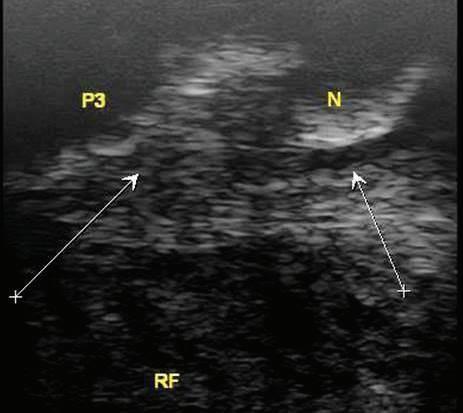

Fig. 5: Left hind suspensory origin is thickened with an inhomogeneous fiber pattern. The origin enthesis is irregular compared to the right hind. The horse demonstrated a mild left hind lameness but no obvious enlargement on palpation.

Figure 5: Left hind suspensory origin is thickened with an inhomogeneous fiber pattern. The origin enthesis is irregular compared to the right hind. The horse demonstrated a mild left hind lameness but no obvious enlargement on palpation. Image courtesy of Dr. Richard D. Mitchell.